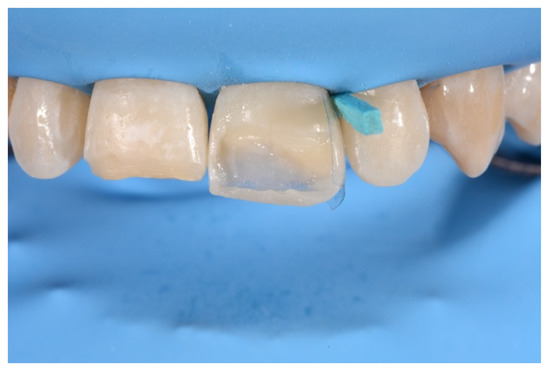

- Molding palatal wall and incisal margin;

- Building interproximal walls with matrices;

- Layering free-hand buccal surface.